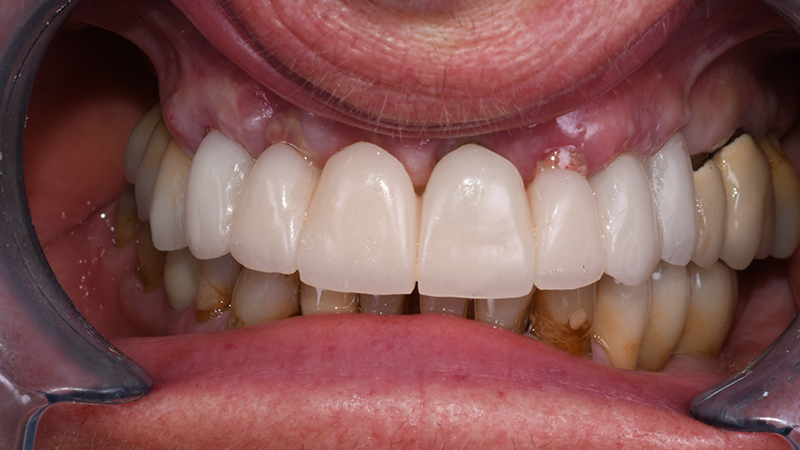

Le fixtures implantari sono state inserite seguendo il planning pre-chirurgico (Figs. 10, 11) in posizione 13-21-23-24. Lo spazio presente tra la componente vestibolare di ciascun impianto e l’osso vestibolare (jumping distance) e gli alveoli post-estrattivi non riceventi impianti, hanno ricevuto l’innesto di sostituto osseo xenogenico collagenato di origine suina (The Graft, Purgo, Challans, Francia) (Figs. 12, 13, 14) dopo aver posizionato i Multi-Unit abutment (MUA). La protesi provvisoria è stata avviata entro 24 ore dal termine della chirurgia (Figs. 15, 16).

Fig. 15 - Visione frontale intra-orale dopo applicazione di protesi provvisoria a carico immediato

Fig. 16 - Sorriso in visione frontale extra-orale dopo applicazione di protesi provvisoria a carico immediato